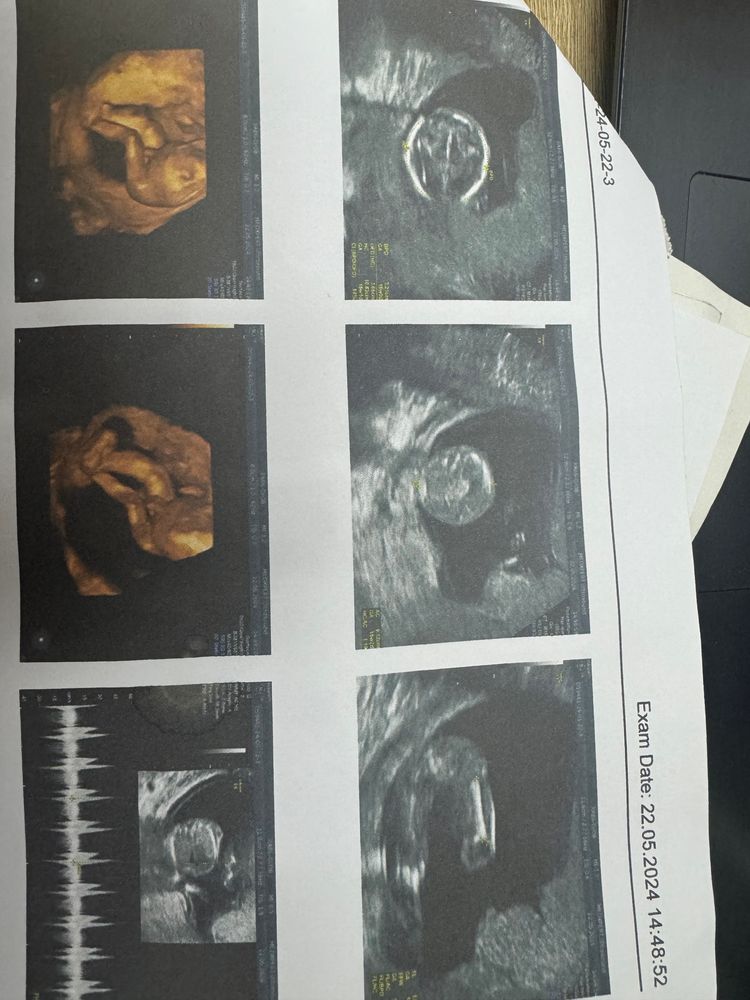

Asel в Благополучная беременность год УЗИ в 14 недель УЗИ, КТГ, доплер УЗИ в 14 недель пожалуйста кто разбирается это девочка да Посмотрите еще 20 записей на эту тему Лучший ответ Надежда я мальчика вижу 10.07.2024 Ответить Отменить Ответить Гроза Райисполкома Это мальчик) 10.07.2024 Ответить Serenity Вроде очень на мальчика похоже 10.07.2024 Ответить Вероника Какая милота 10.07.2024 Ответить Asel 10.07.2024 Ответить Asel Asel, вот еще )) 10.07.2024 Ответить Вероника А на УЗИ не сказали? 10.07.2024 Ответить Asel Вероника, нет , воообще отказался сказал только во втором скрининге точно скажу сказал 10.07.2024 Ответить Без одного дня 6 недель, узи Шейка и воды в 29 недель Чаты Беременных Выберите чат: Январята-2026 Февралята-2026 Мартята-2026 Апрелята-2026 Майчата-2026 Июнята-2026 Июлята-2026 Августята-2026